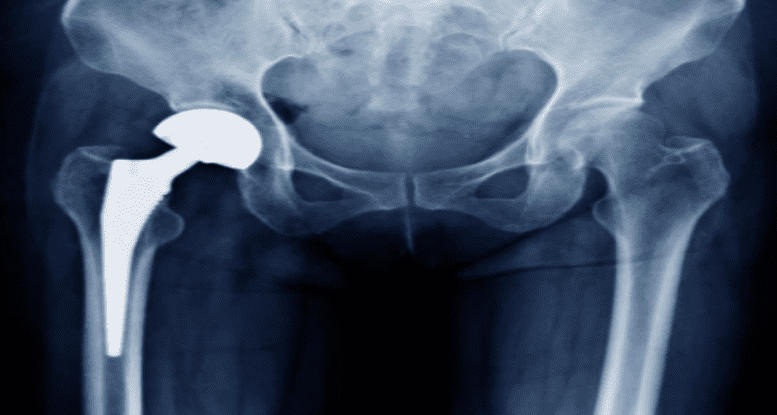

Reemplazo articular

Artroplastia de Rodilla y Cadera, para casos avanzados de Gonartrosis o Coxartrosis, con los mejores implantes del mercado, con técnicas quirúrgicas actualizadas y una recuperación de la movilidad y calidad de vida de forma inmediata.